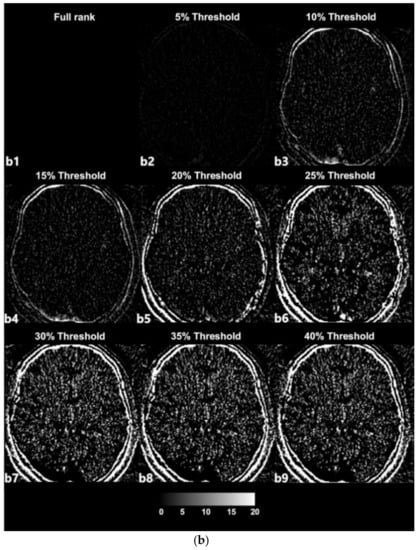

The SVD-based denoising technique was applied to 20 CTP datasets. Each dataset was reconstructed with singular values that were higher than the 5%, 10%, 15%, 20%, 25%, 30%, 35%, and 40% threshold values. Figure 3a depicts an example of denoised images corresponding to increasing thresholds. Figure 3b presents images with noise that were reconstructed with singular values lower than each threshold value and that were separated from the original full-rank image. In an example dataset, a full rank image (original noised Image) includes 27 singular value (Signal Component, SC) components. As shown in Figure 3a,b, the removal of larger amounts of Gaussian noise on an image is observed when the image is reconstructed with a smaller number of SCs (i.e., a larger number of low singular values were excluded).

(a) Example of denoised images based on thresholding values; a1—original image, a2–a9—denoised images. (b) Example of separated noise components in accordance with thresholding; b1—no noise component was separated from the original image, b2–b9—noise components separated from the original image corresponding to Figure 3.

The term ‘rank’ refers to the number of singular values added to reconstruct a single image [28,29]. The number of singular values in a rank was determined in relation to the threshold value. We selected the 2nd component of the diagonal S matrix as the threshold value on an experiential basis; there is no golden rule to guide the selection of the threshold value because the boundaries of the signal and noise components are still vague and unclear (Figure 2). Thresholding was the process used to approximately classify the singular values in terms of signal components and noise components. The singular values that were lower than the set threshold percentage value (2nd component) were assumed to be singular value noise components in every condition and were subsequently reconstructed into a noise-containing image (Figure 3b). In contrast, the singular values that were higher than the set threshold percentage value (2nd component) were assumed to be singular signal components in every condition and were subsequently reconstructed into a denoised image (Figure 3a).

In the used dataset, the full-rank image (original image, a1) included 27 SCs (Figure 3a), i.e., the 1st to the 27th components, which were in decreasing order of magnitude and were not yet classified. In the case of Figure 3a from a2 to a9, with increasing threshold percentages, larger numbers of components were classified as noise components, resulting in denoised images. For example, in the case of (Figure 3a, a2), the 1st to the 20th singular values were included to reconstruct the denoised image labeled as the 5% threshold image, and the 21st to the 27th singular values that were lower than 5% of the 2nd component were separated from the full-rank image and used to reconstruct the separated noise-containing image (Figure 3b, a9). The image a9 that is labeled as 40% of the threshold image was reconstructed including only the 1st and 2nd singular values by separating the largest number of SCs (25 SCs) from the full-rank image. Nonetheless, the image still appears to exhibit sufficiently high image quality. Regarding image a9, the 1st and 2nd singular values are predominantly depicted as providing diagnostic information. However, it is difficult to confirm that the image at the 40% threshold is the best one, as it simply involves the separation of a larger number of noise-related patterns; reducing the noise on a medical image is inevitably a trade-off for acquiring diagnostic information.